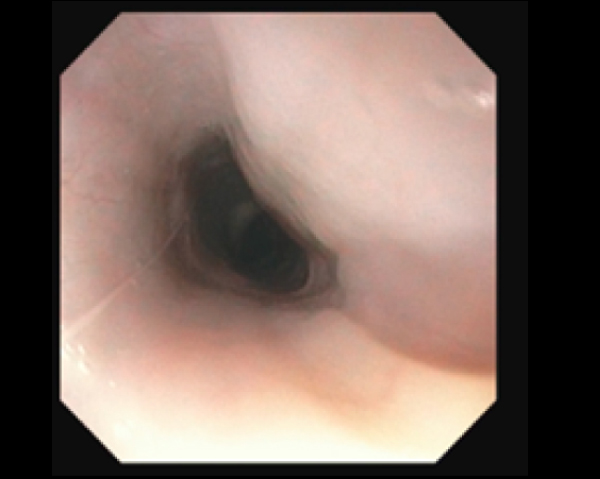

内視鏡で狭窄部位を確認

内視鏡の位置をCアームで確認し正確に場所の把握が可能

2.8mmと5mmの内視鏡を用いて気管と食道両方の観察・生検が同時に実施可能